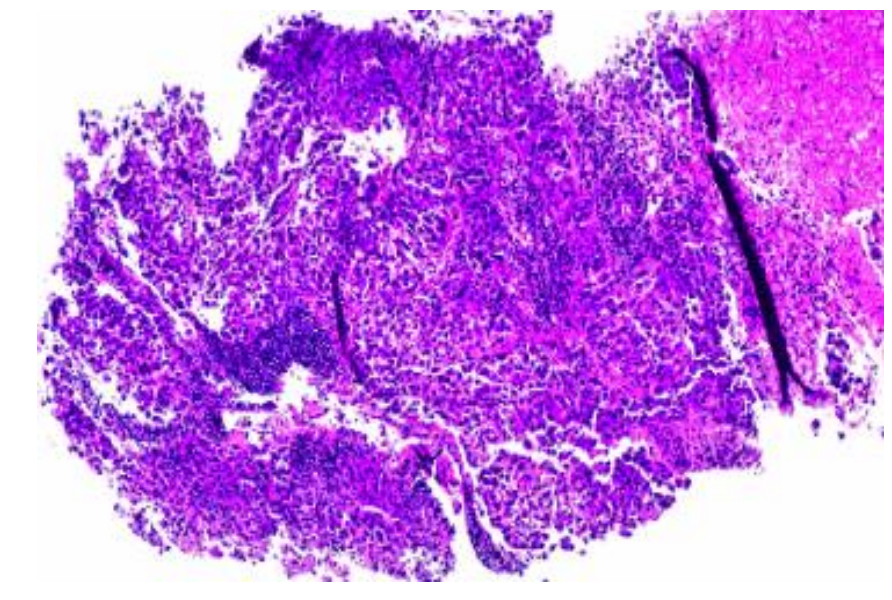

图片

图2. 右侧淋巴结活检的病理切片。肿瘤细胞对PAN-K、Glypican-3、HepPar1和抗精氨酸酶呈阳性染色,而对p40和CEA-poly呈阴性染色,从而确诊为转移性肝细胞癌。